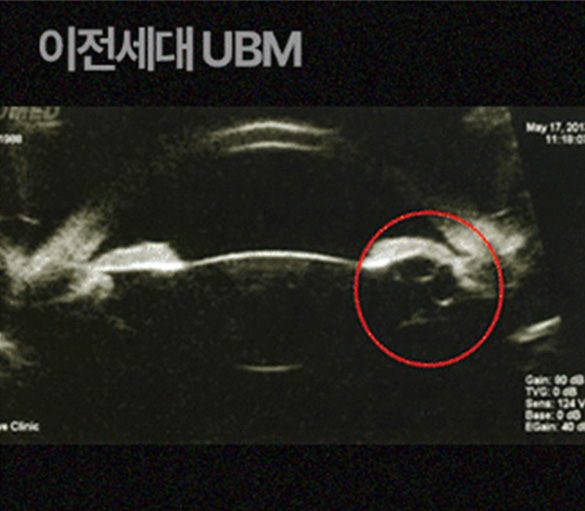

3D안구 입체 모델링

정밀 측정해 사전 부작용을 예방합니다

오차없는 안구공간을 입체적으로 측정하여 사전 부작용을 예방합니다

통해

해상도의 차이로 발생하는

작은 오차까지 예방합니다